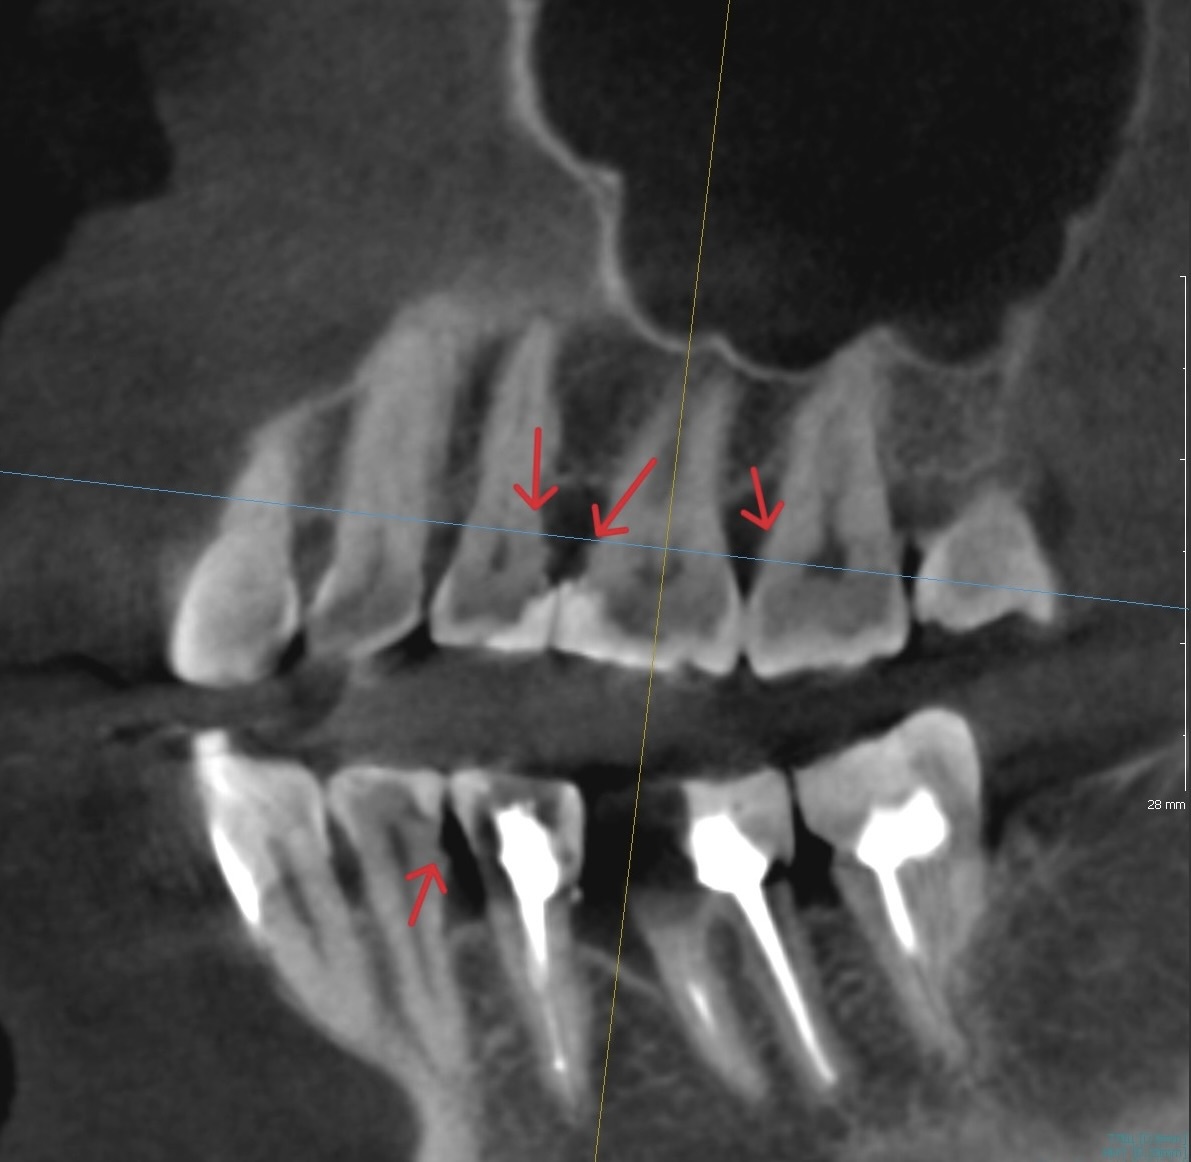

Как врач понимает, что под десной находятся зубные отложения

Вообще, опытный гигиенист и пародонтолог видят отложения по косвенным причинам - покраснение, синюшность дёсен, отёчность, лакированный блеск, проблемы с десневыми сосочками (они могут быть сплющенными, могут быть чрезмерно объёмными). Иногда не нужно даже залезать под десну - достаточно сделать КТ:

Поддесневые зубные отложения

На снимке видно корни, а между ними - острые, довольно ровные “шипики”.

Это не анатомия коня такая, это и есть

минерализованный камень.

Если они видны на КТ, значит, плотность у них сопоставима с плотностью корня.

А вокруг этого плотного остова всегда есть более мягкие отложения, которые томограф, пока что, не видит. Но это вопрос времени.

Камни не обязательно проявляют себя ярко, иногда они сглажены визуально. Но они точно заметны, на корнях не должно быть наростов: